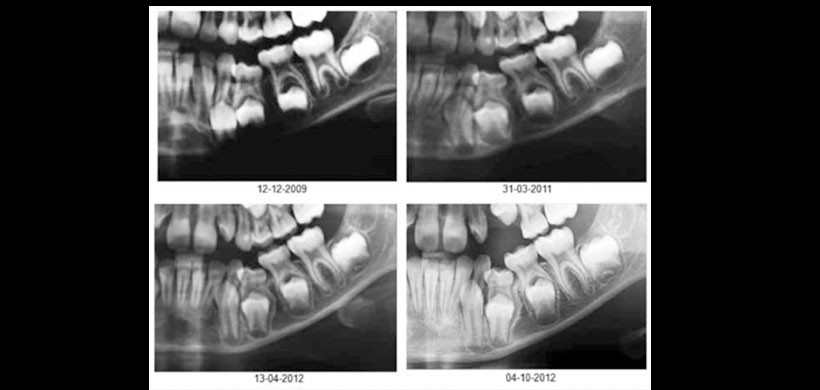

Al examen radiográfico, se muestra una secuencia de radiogra as panorámicas (2009- 2012) donde se observa la infraoclusión severa del diente 7.4 (Figura 2). La interpretación radiográfica revela que el diente 7.4 se encuentra semi sumergido, en distoversión e impactado en la zona mesiocervical del diente 7.5, e impactado a su vez por distal del diente 7.3.

Al efectuar un estudio comparativo entre las radiografías panorámicas que porta el paciente, se observa que el diente 7.4 no ha presentado cambios posicionales desde Diciembre 2009, observándose solamente una progresión de la reabsorción radicular, evaluada en los exámenes actuales. El germen del diente 3.4 se presenta en una posición discretamente más hacia basilar en comparación a las piezas vecinas y homóloga contralateral.